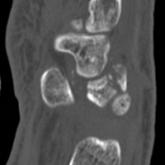

Translunate, Transradial, Transtriquetral, Transtrapezoid Perilunate Dislocation With Multiple Metacarpal Neck Fractures

We report a rare case of translunate, transradial, transtriquetral, transtrapezoid perilunate dislocation with multiple metacarpal neck fractures...